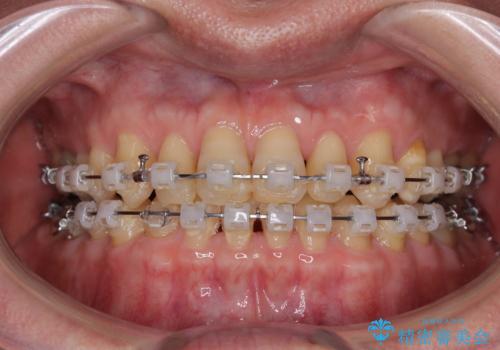

- 矯正装置

- クリアブラケット

- 前歯のデコボコと隙間の空いた歯列を気にして来院された患者様です。

下顎前歯が隠れるほどのディープバイトにより、強い咬合力と突き上げで上顎歯列に隙間が空いている状態でした。

手前に傾斜している奥歯をワイヤー装置で立ち上がらせ、咬み合わせの高さを挙上することで突き上げを解消し、空隙歯列を改善していくこととしました。